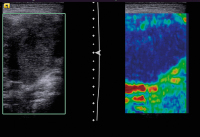

Lymphknoten-Elastographie

Abbildung 7: Qualitative Elastographie. In dieser Messung stellt sich die in der linken Bildhälfte partiell abgebildete Lymphknotenmetastase eines Plattenepithelkarzinoms in der rechten Bildhälfte als in Blau kodierte harte Läsion dar. In Rot und Grün die eher weich kodierten Areale.

Abbildung 8: Elastographie. Hier stellen sich beim gleichen Patienten wie in Abbildung 7 und gleichen Lymphknoten die harten Areale in der rechten Bildhälfte dunkel dar. Weiche Areale werden hell kodiert. Eine definierte mechanische Energie wird über den Ultraschallkristall eingebracht.